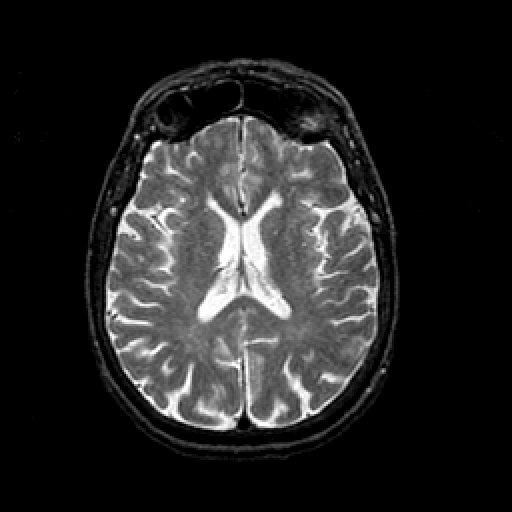

T2-weighted structural MR: Slice 31

Slice 31